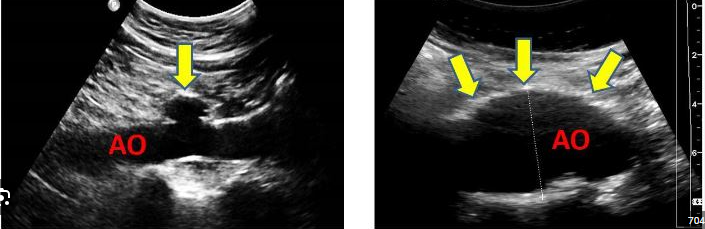

Mild AI

Jet height/width

vena contracta

PHT

Spectral doppler waveform

flow reversal

jet area

regurgitant oriface area

LV size

• Jet height/width (LVOT) <25%

• Vena contracta width less than 0.3 centimeters

• Pressure half-time greater than 500 milliseconds

• Light or incomplete density of the spectral Doppler waveform

• Only brief or no diastolic flow reversal in the descending aorta

• Jet area less than 20% of the left ventricle

• Regurgitant orifice area less than 0.10 cm2

• Normal left ventricular size

Severe AI

Jet height/width

vena contracta

PHT

Spectral doppler waveform

flow reversal

jet area

regurgitant oriface area

LV size

• Jet height/width (LVOT) ≥ 65%

• Vena contracta width greater than 0.6 centimeters

• Pressure half-time less than 200 milliseconds

• Holodiastolic flow reversal is seen in the descending aorta (supraternal window)

• Jet area greater than 40% of the left ventricle

• Regurgitant orifice area ≥ 0.30 cm2

• Dense spectral Doppler signal

• Left ventricular enlargement

AI PHT

mild

moderate

moderatley severe

severe

jet height (PLAX)

mild

moderate

moderatley severe

severe

Jet height / LVOT Height (PLAX)

mild

moderate

moderatley severe

severe

Jet area / LVOT area (PSAX)

mild

moderate

moderatley severe

severe

Vena contracta width (cm) (PLAX)

mild

moderate

severe

mild

< 0.3 cm

moderate

0.3 - 0.6 cm

severe

> 0.6 cm

Jet area / LVOT area (%) (PSAX)

mild

moderate

severe

mild

<4%

moderate

4 - 24%

25 - 59%

severe

>60%

Flow reversal (descending aorta, suprasternal notch)

mild

moderate

severe

mild

brief or none

moderate

severe

holodiastolic

AO PHT (ms)

mild

moderate

severe

mild

>500 ms

moderate

500 - 350 ms

350 - 200 ms

severe

< 200 ms

Spectral doppler waveform

mild

moderate

severe

mild

Light, may not be complete, parabolic

moderate

severe

Dense

AI Jet area

mild

moderate

severe

mild

< 20% of LV

moderate

severe

> 40% of LV

Regurgitation volume (mL/beat)

mild

moderate

severe

mild

<30 mL/beat

moderate

30 - 44 mL/beat

45 - 59 mL/beat

severe

≥ 60 mL/beat

Regurgitaion fraction (%)

mild

moderate

severe

mild

< 30%

moderate

30 - 39%

40 - 49%

severe

≥ 50%

Effective Regurgitant oriface area (cm²)

mild

moderate

severe

mild

< 0.10 cm²

moderate

0.10 - 0.19 cm²

0.20 - 0.29 cm²

severe

≥ 0.30 cm²

LV Size

mild

moderate

severe

mild

normal

moderate

severe

Enlarged